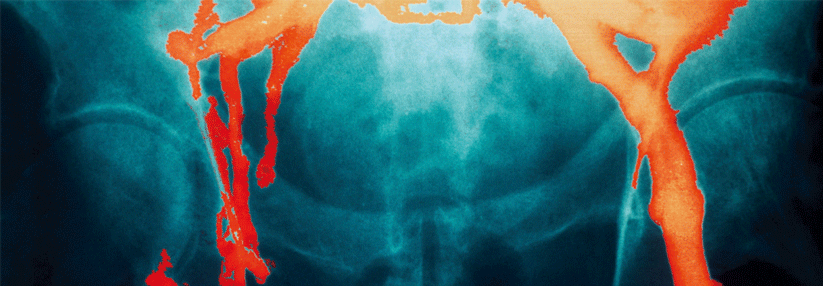

Einbezogen in die Nichtunterlegenheitsstudie waren 1858 vor einem Eingriff stehende Erwachsene mit einem mäßigen bis hohen VTE-Risiko, die randomisiert entweder LMWH oder LMWH plus Kompressionskniestrümpfe erhielten. Primäres Studienziel waren neu aufgetretene, per Bildgebung nachgewiesene VTE mit oder ohne Symptome oder eine Lungenembolie innerhalb von 90 Tagen nach dem Eingriff.

Solche Ereignisse traten bei 1,7 % der Patienten in der LMWH-Gruppe und bei 1,4 % in der LMWH-Kompressionstrumpf-Gruppe auf. Damit bestätigt sich die Nichtunterlegenheit der alleinigen LMWH-Therapie aus Sicht von Joseph­ Shalhoub­ vom Imperial College Healthcare NHS Trust in London und Kollegen. Auch bei der Auswertung von Patienten-Subgruppen (älter vs. jünger als 65 Jahre oder mäßiges vs. hohes Risiko) ergaben sich keine Vorteile für das zusätzliche Strümpfetragen.